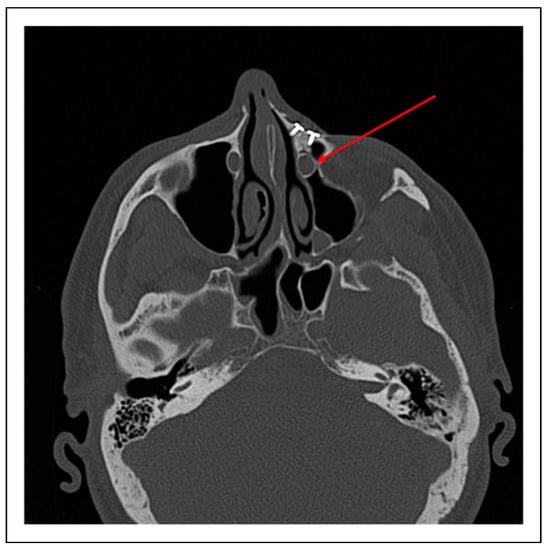

Case 2